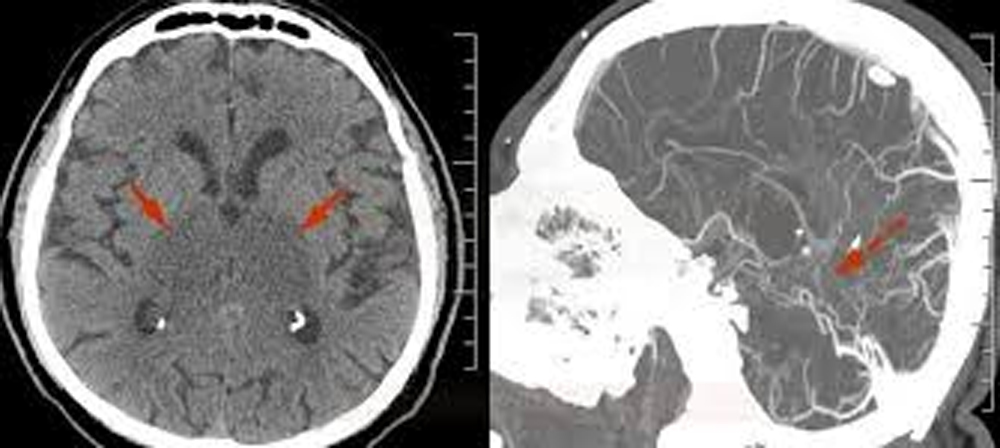

Cerebral Venous Thrombosis is a rare but potentially fatal condition in which a blood clot forms in the venous sinuses of the brain. These sinuses are responsible for draining blood from the brain. When a blockage occurs, it can lead to increased pressure, brain swelling, or haemorrhage, which, in severe cases, can cause permanent brain damage. As per Dr Jaideep Bansal, HOD and Senior Consultant, Neurology Department, Saroj Super Specialty Hospital, women are more susceptible to suffering from Cerebral Venous Thrombosis because they have relatively more hormonal changes.

CVT is considered a rare type of stroke that affects about 5 people per million annually. In pregnant women, the risk increases due to hormonal changes, increased blood volume, and a heightened propensity for clotting during pregnancy and the postpartum period.While CVT in children is rare, newborns are most at risk in their first month of life.